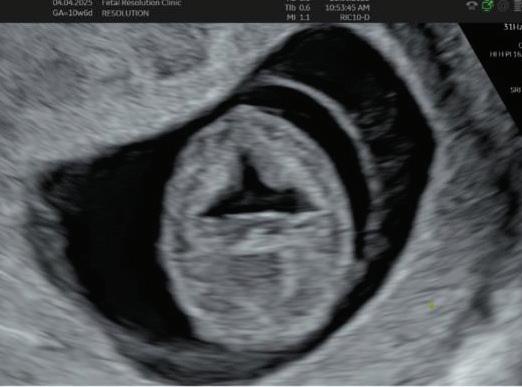

1. EARLY PREGNANCY SCAN (6–10 WEEKS)

Findings:

• Gestational sac at ~4.5–5 weeks-Appears as anechoic fluid filled structure surrounded by a decidual reaction (Double Decidual sac sign).

• Measure Mean sac diameter .

• Yolk sac appear around ~5–5.5 weeks.

• Embryo with cardiac activity around 6 weeks.

1. Establish viability and Confirmation of intrauterine pregnancy/ uterine integrity.

2. Accurate dating of pregnancy.

3. Early assessment of fetal anatomy.